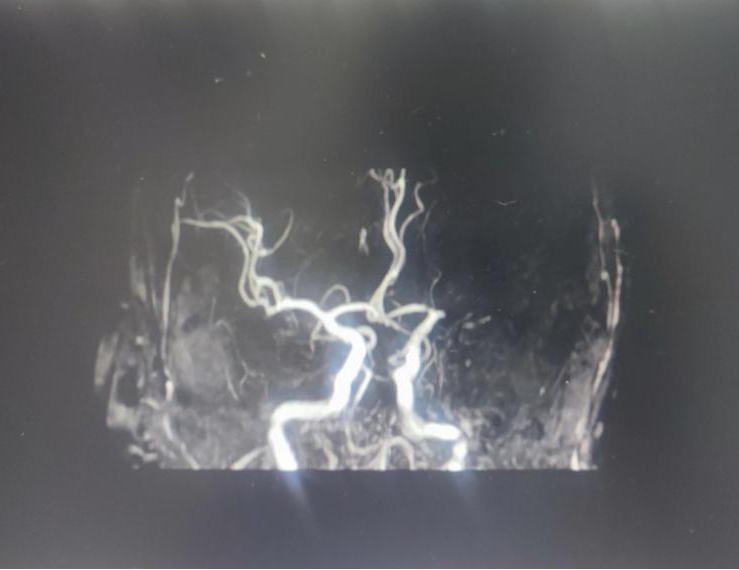

高龄患者静脉溶栓后又现再发闭塞神经介入团队两次勇闯“鬼门关” 8月3号和4号是徐大爷一辈子最难忘的两天。两天,徐大爷从“鬼门关”被救回来两次。徐大爷...